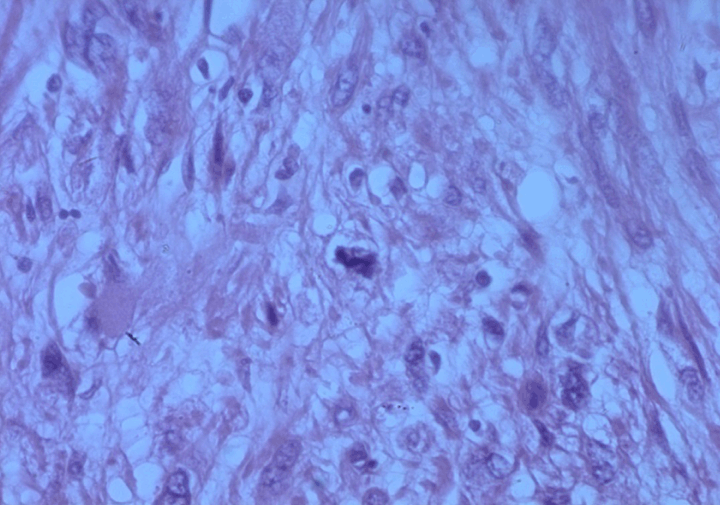

Microscopic examination showed a high degree of cellular proliferation composed of spindle cells with round or oval-shaped nuclei implicating a storiform growth pattern (Figure 1). Necrosis was evident. Immunohistochemical examination revealed that the tumor cells were strongly positive for calponin, epithelial membrane antigen (EMA) smooth muscle actin and vimentin (Figure 2) and (Figure 3) but negative for S-100 and myogenic regulatory protein (MyoD1) proteins. The combined histologic and immunohistochemical findings were diagnostic of primary high-grade intratesticular leiomyosarcoma. With 24 months of follow-up, which included computed tomography scan of the abdomen, pelvis, bone, and chest, the patient remained free of disease.

Figure 2: Diffuse mesenchymal proliferation of malignant spindle shaped cells with eosinophilic, fibrillary cytoplasm and atypical nuclei displaying mitotic figures (H&E stain, x400).